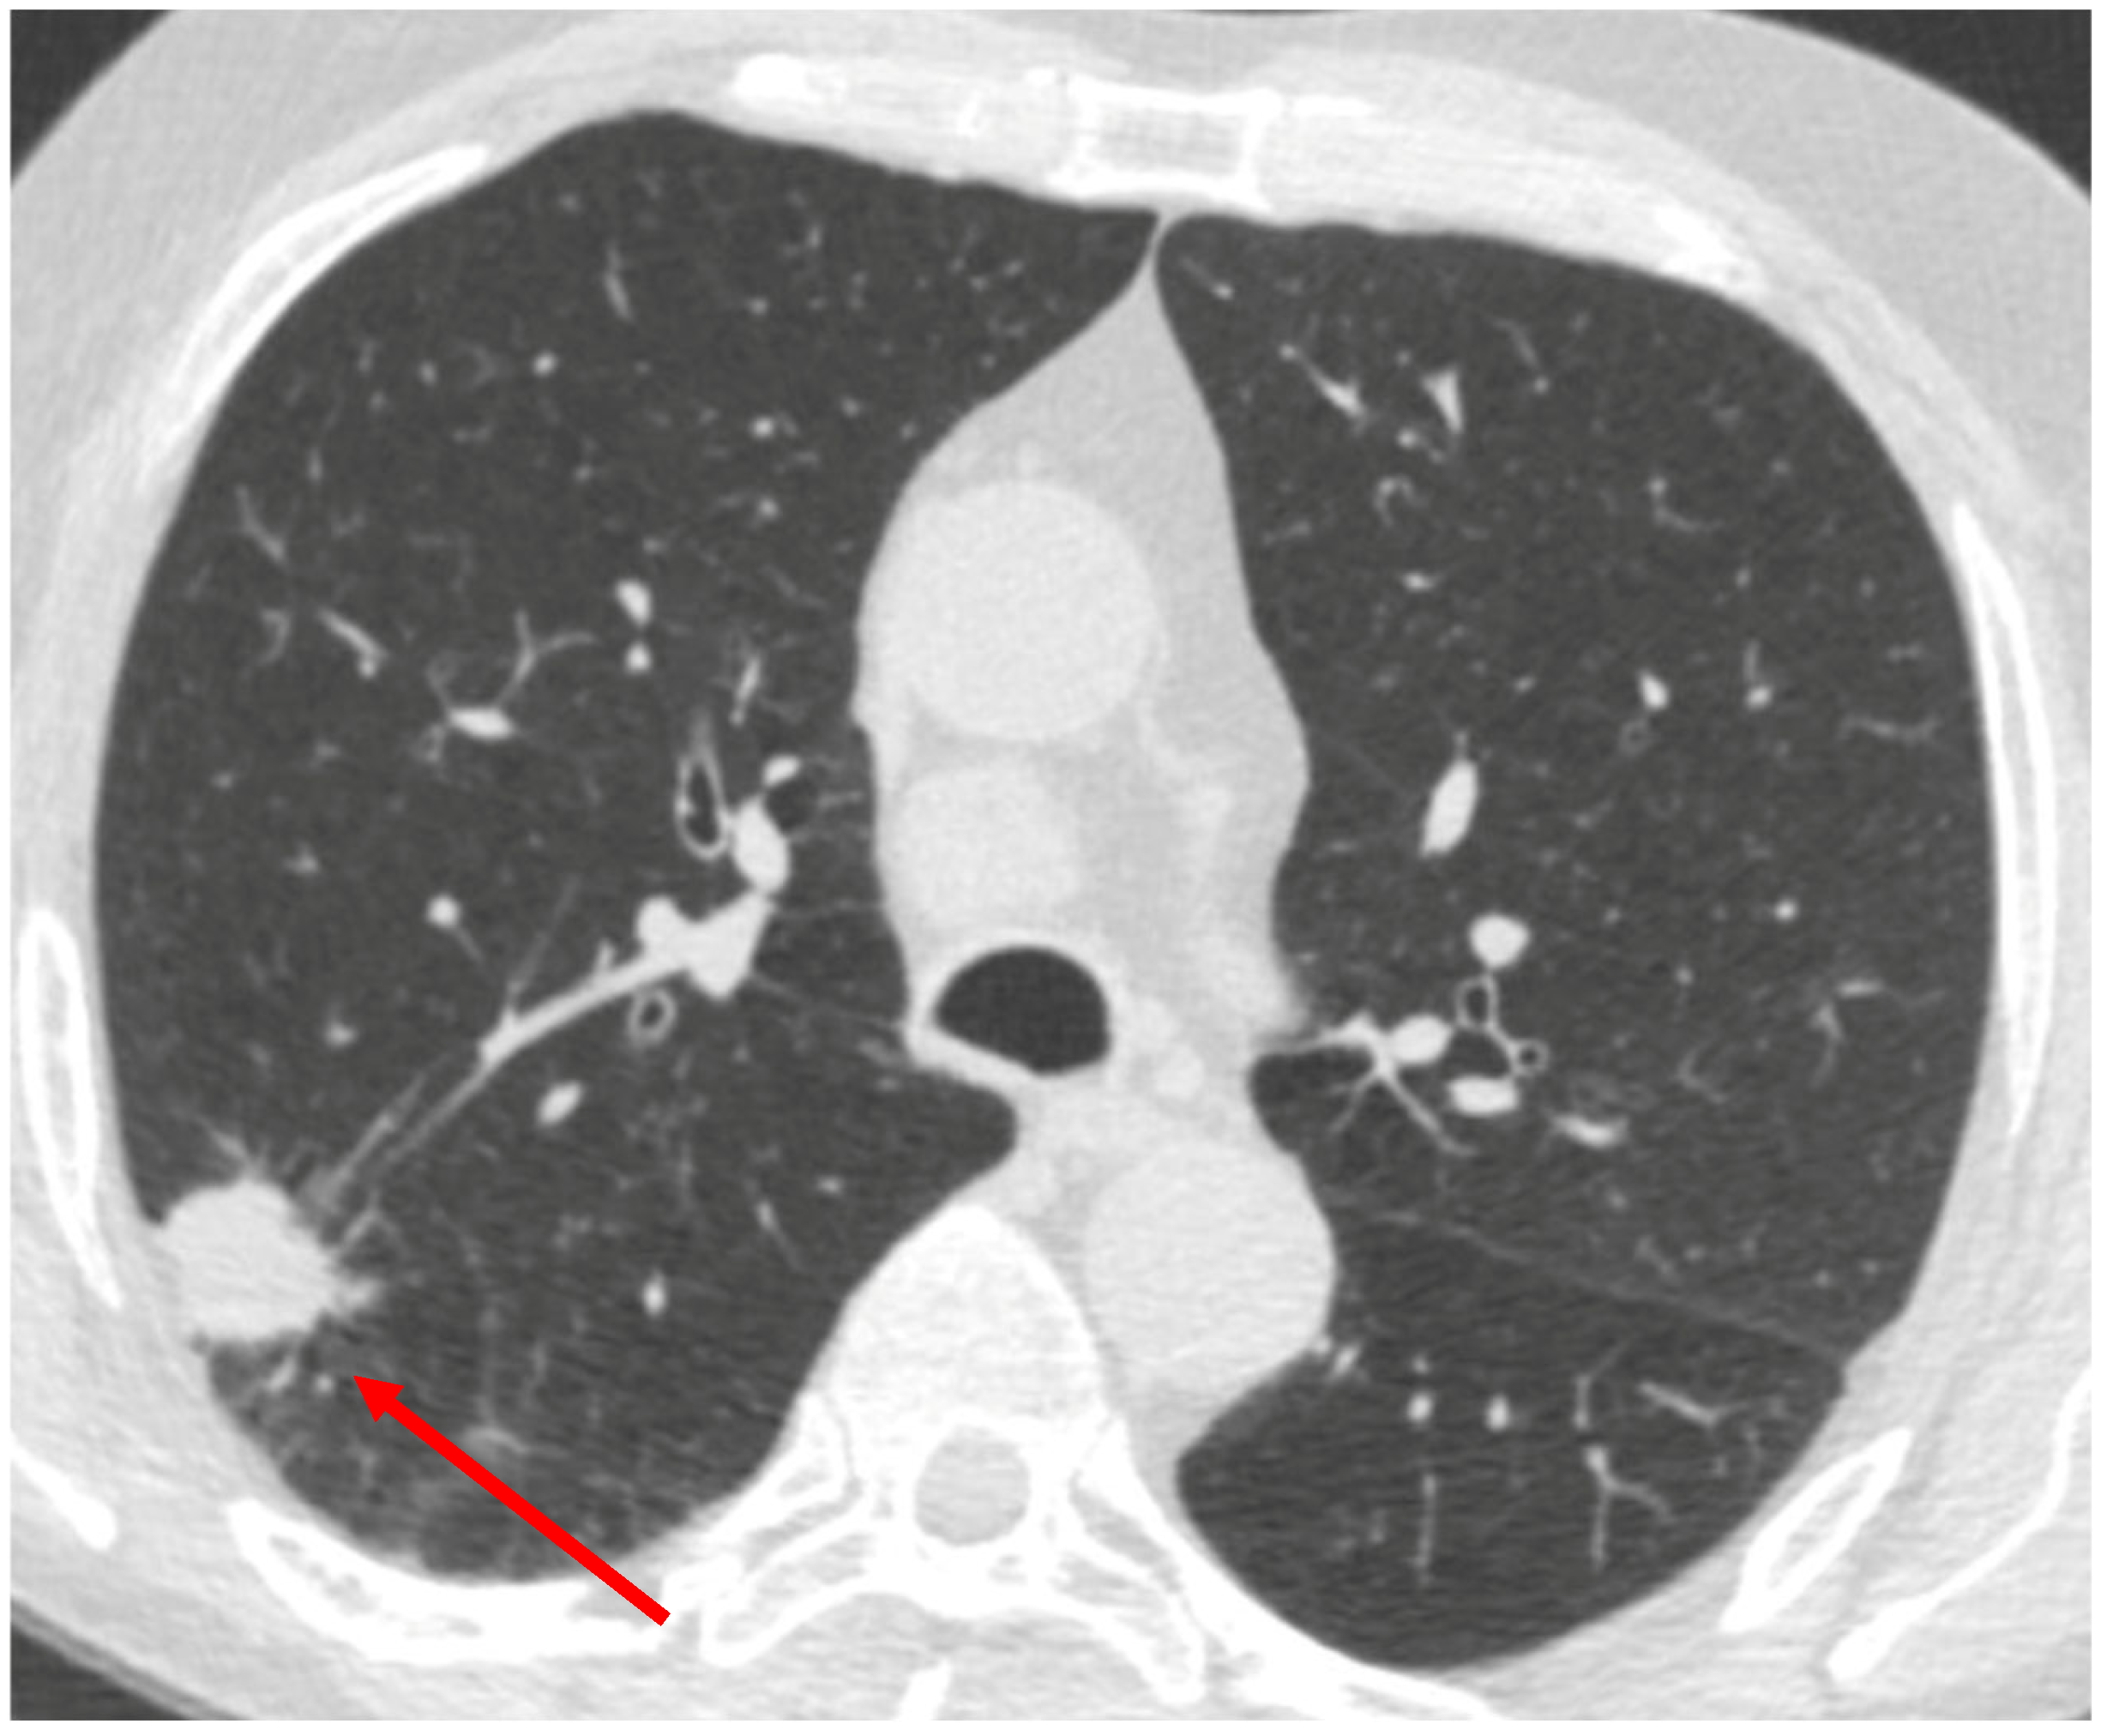

2. Clinical Challenge: A Representative Case